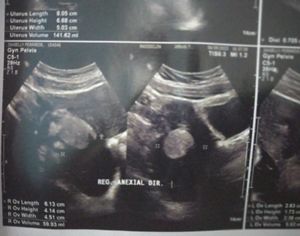

Olá, recentemente descobri que estava com um tumor no ovário direito e que pelo tamanho que está, é necessário cirurgia e no momento nem eu e nem minha família temos condições de pagar o valor. Peço a ajuda de vocês qualquer valor é bem vindo. Obrigada

Olá, recentemente descobri que estava com um tumor no ovário direito causando muita dor e que pelo tamanho que está, é necessário cirurgia e no momento nem eu e nem minha família temos condições de pagar o valor. Peço a ajuda de vocês qualquer valor é bem vindo. Obrigada